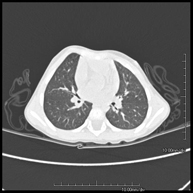

- TC Tórax

Prueba diagnóstica que consiste en obtener imágenes del tórax de alta definición anatómica (pulmones, corazón, mediastino, grandes vasos, caja torácica, etc.) mediante el empleo de un equipo de TC (Tomografía Computarizada). Dichas imágenes se estudian posteriormente en una estación de trabajo que permite reconstrucciones bidimendionales en diferentes planos del espacio y también reconstrucciones 3D (volumétricas). Algunos estudios requieren el empleo de contraste yodado para mejorar la definición de las imágenes. - Angio-TC Aorta torácica